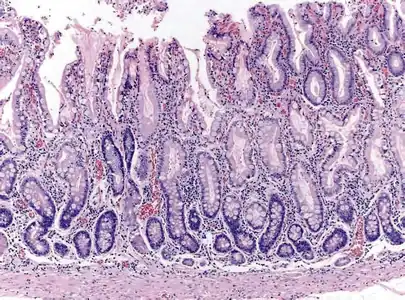

Atrophic gastritis under low power. H&E stain.

Autoimmune metaplastic atrophic gastritis (AMAG) is an inherited form of atrophic gastritis characterized by an immune response directed toward parietal cells and intrinsic factor.[6] The presence of serum antibodies to parietal cells and to intrinsic factor are characteristic findings. The autoimmune response subsequently leads to the destruction of parietal cells, which leads to profound Achlorhydria (and elevated gastrin levels). The inadequate production of intrinsic factor also leads to vitamin B12 malabsorption and pernicious anemia. AMAG is typically confined to the gastric body and fundus.